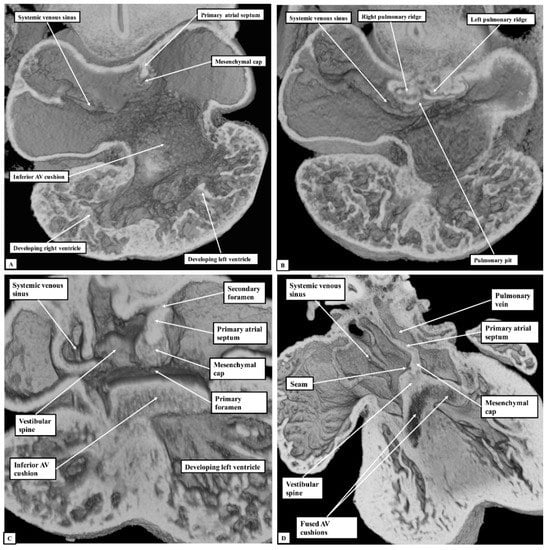

Figure 6. The images show sections prepared in the four-chamber plane from mouse embryos sacrificed at the sixteenth day of development (E15.5). (Panel A) shows the normal arrangement, with the primary atrial septum forming the floor of the oval fossa (double-headed white arrow). (Panel B) shows an “ostium primum” defect, with common atrioventricular junction due to failure of formation of the vestibular spine. (Panel C) shows a large defect in the primary septum adjacent to the vestibular spine, thus producing a caudal defect within the oval fossa. The double-headed white arrow shows the margins of the oval fossa. AV—Atrioventricular.

If development proceeds in a normal fashion, the margins of the oval fossa are intact by E15.5. We examined episcopic datasets prepared from 48 mouse embryos at this stage. In 38 of the mice, the findings show the normal arrangement, with the primary septum folded on itself cranially, its length being considerably greater than the length of the fossa (Figure 6A). In these 38 datasets, the vestibular spine and mesenchymal cap fused together to form the caudal rim of the fossa, with obliteration of the seam initially seen between the two components during E13.5 (Figure 5D). The primary septum now forms the floor of the oval fossa, with the space between its cranial margin and the atrial roof forming the oval foramen, or secondary atrial foramen. The excessive length of the septum relative to the dimensions of the fossa provides the mechanism that permits closure of the foramen subsequent to birth. In 10 of the datasets prepared from mice sacrificed at E15.5, however, we found deficiencies of either the inferior rim of the oval fossa, or the attachment of the leading edge of the primary septum. In two, the findings could be attributed to the failure of formation of the vestibular spine (Figure 6B), with additional failure of growth of the primary septum in one of the two. In both, the lack of growth of the spine was associated with persistence of a common atrioventricular junction, with the atrioventricular cushions fused to each other, and also to the crest of the muscular ventricular septum, in other words producing an “ostium primum” defect. In four further datasets, although the vestibular spine had protruded in anticipated fashion to form the caudal margin of the oval fossa, thus separating the right and left atrioventricular junctions and forming the caudal rim of the fossa, the primary septum itself was deficient adjacent to the caudal rim, thus producing a hole in the floor of the fossa adjacent to its antero-inferior buttress, in other words, an “ostium secundum” defect (Figure 6C) The defect was large in two of the datasets but smaller in the remaining two. In the remaining four datasets, the mesenchymal cap had failed to fuse with the vestibular spine. The spaces in the floor of the oval fossa in these four hearts (Figure 7), therefore, are directly comparable to the vestibular defects found in our autopsied hearts.